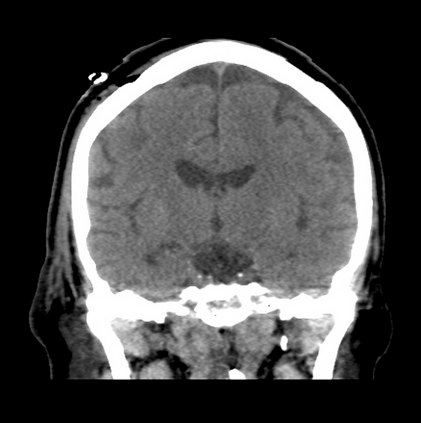

In this study, we aim to initiate the development of Radiology Foundation Model, termed as RadFM.We consider the construction of foundational models from the perspectives of data, model design, and evaluation thoroughly. Our contribution can be concluded as follows: (i), we construct a large-scale Medical Multi-modal Dataset, MedMD, consisting of 16M 2D and 3D medical scans. To the best of our knowledge, this is the first multi-modal dataset containing 3D medical scans. (ii), We propose an architecture that enables visually conditioned generative pre-training, allowing for the integration of text input interleaved with 2D or 3D medical scans to generate response for diverse radiologic tasks. The model was initially pre-trained on MedMD and subsequently domain-specific fine-tuned on RadMD, a radiologic cleaned version of MedMD, containing 3M radiologic visual-language pairs. (iii), we propose a new evaluation benchmark that comprises five tasks, aiming to comprehensively assess the capability of foundation models in handling practical clinical problems. Our experimental results confirm that RadFM significantly outperforms existing multi-modal foundation models. The codes, data, and model checkpoint will all be made publicly available to promote further research and development in the field.